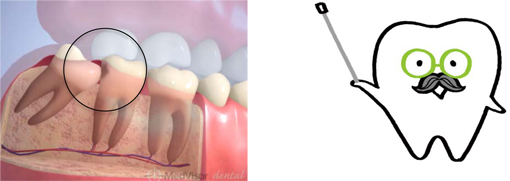

3. ほぼ真横にはえている

|  |

この状態の親知らずは生える事はありません。

見た目も歯茎の中や骨の中にうまっている為解りません。

歯科医院にてレントゲンを撮る事で親知らずがあるかないかが解りますので、一度レントゲンを撮って確認してみましょう。

症状として

- 歯ぐきが痛くなる

- 顎が痛くなる

- 口が開かなくなる

これらの諸症状が一度でも出た事がある方は、抜歯を考えた方が良いでしょう。